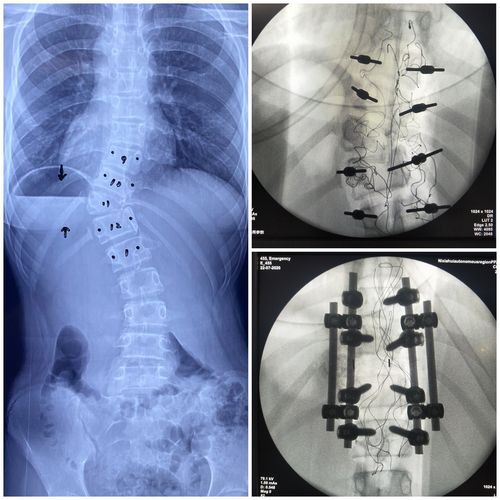

典型病例3:先天性脊柱侧凸

女/11/先天性脊柱侧后凸

病例分享 – - 先天性脊柱侧弯 t11半椎体畸形